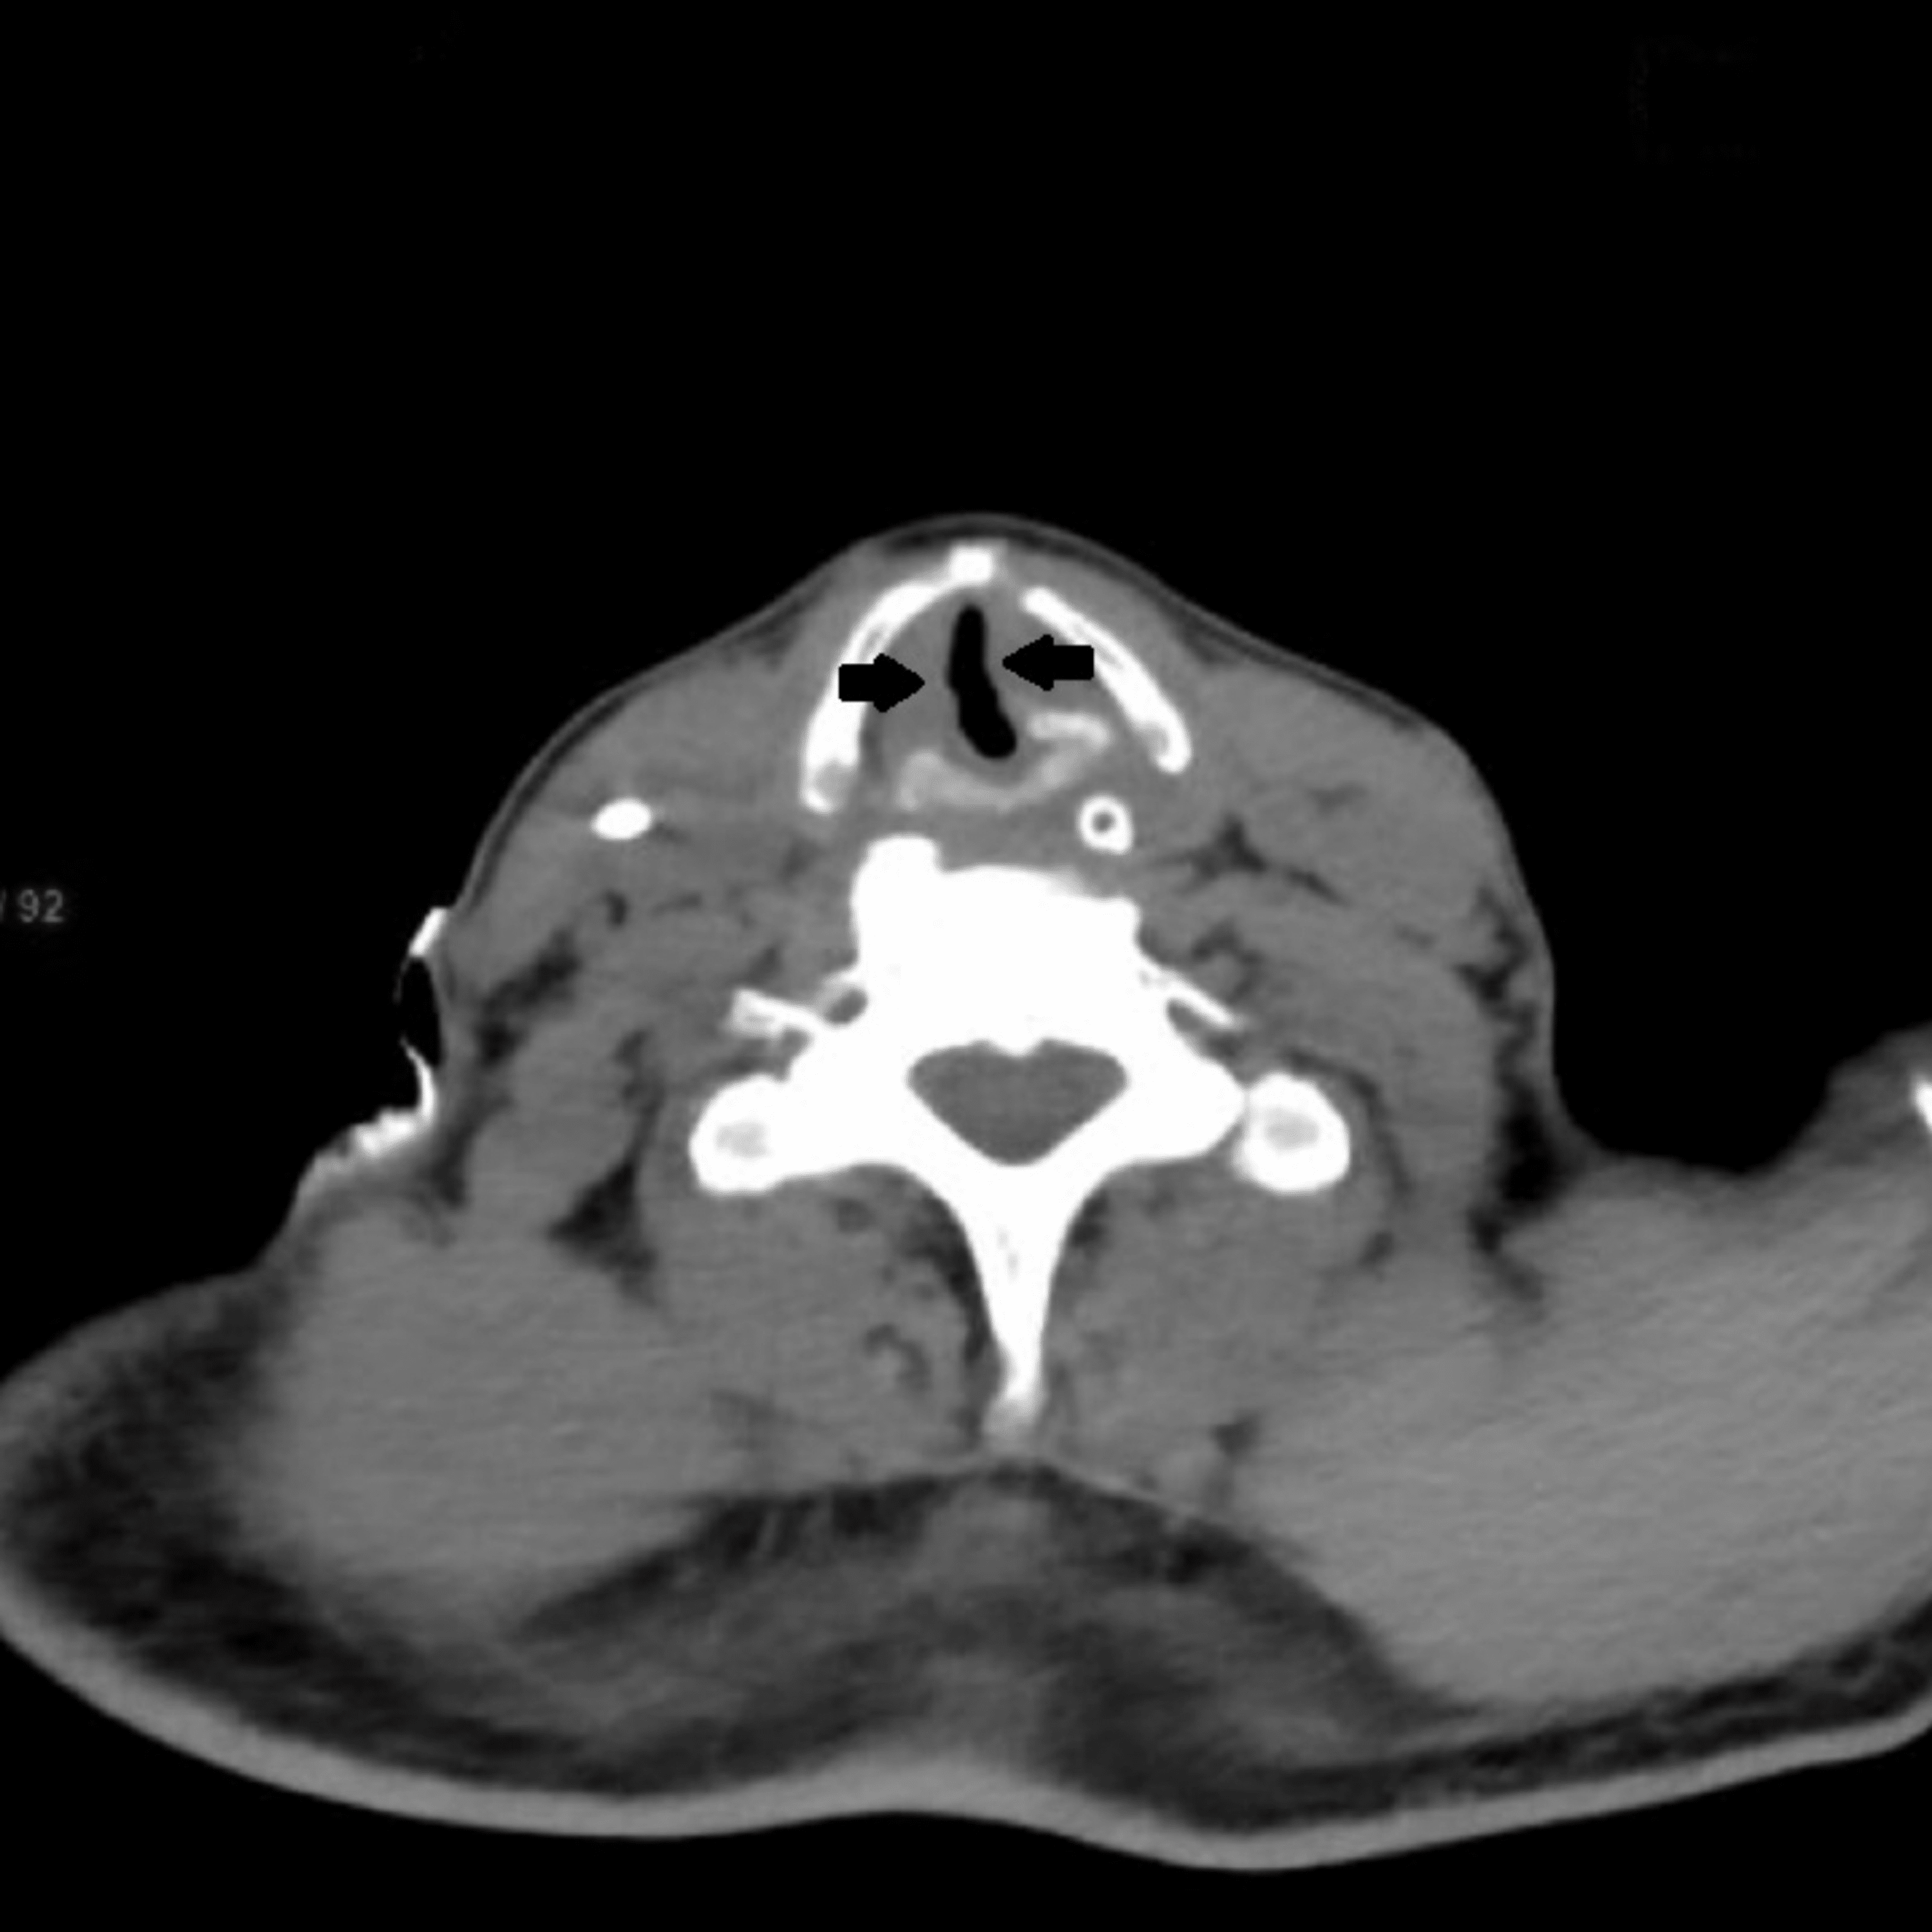

From www.cureus.com

Postextubation Stridor in a Case of Intracranial Bleed Assessing Extubation Airway Edema Skill level of junior staff in unit overnight. 5% patients experience severe upper airway obstruction following extubation; Leave the airway exchange catheter in place temporarily to ensure that the airway is patent. Laryngeal edema is a common cause of airway obstruction in the recently extubated intensive care unit (icu) patient. Remember to consider other factors: Laryngeal edema (le) is a. Extubation Airway Edema.